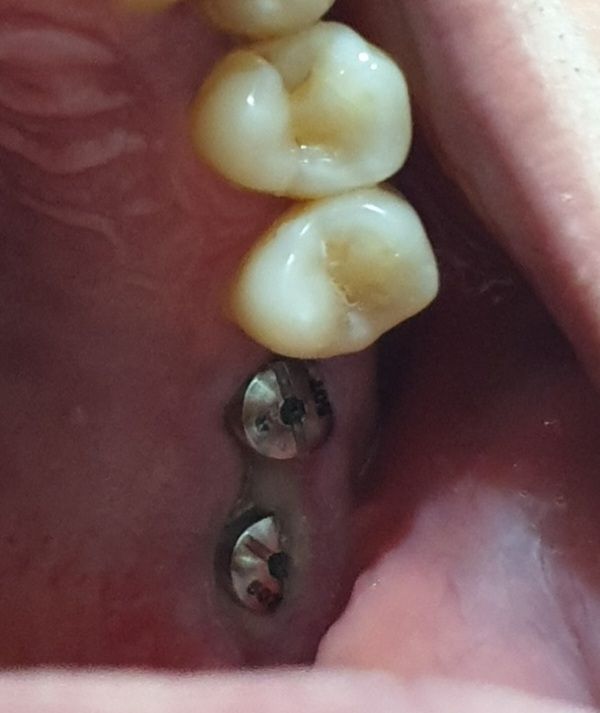

임플란트 나사 식립후 잇몸좀 봐주세요

상악동 거상술 이후 뼈이식 후 거의 6개월정도 지난후 나사를 박았구요 근데 나사박은지 2주가 다되가는데 잇몸 붓기도 덜빠진거같고 잇몸에 하얀부분이 뭔지 궁금합니다 나사주위에 하얀부분하고 원래 잇몸이 나사를 조금 덮어버린거같은데 정상인건지요 ㅠㅠ

나사 식립 후 잇몸 살이 조금씩 차오르면서 생기는 것이며 사진상으로 특별히 문제가 보이지는 않습니다

걱정안하셔도 괜찮아보입니다.

• 안녕하세요 치과의사 김철진입니다. 잇몸이 자라면서 힐링이라는 저 뚜껑을 덮을수도 잇습니다. 기다리셧다가 시간이 지나면 다시 더 긴 힐링으로 교체를 할꺼니 걱정하지 않으셔도 됩니다.

• 정상 잇몸 조직이나 얇아서 하얗게 보이는 것 같습니다 다소 잇몸 증식이 빠른양상인데 치과가면 임플란트 뚜껑을 타고 올라가있는 잇몸을 조금 절제하는 처치를 해줄 수 있습니다

• 현재 사진상 크게 문제가 되는 부분은 없어 보이며, 시간이 지남에 따라 붓기 및 염증이 가라앉게 됩니다. 만약 통증이 동반되는 경우에는 소염진통제 복용이 증상 경감에 도움이 됩니다.

• 임플란트를 하고난 다음에 잇몸이 나사를 덮거나 할 수 있습니다. 나중에 보철물을 할 때는 해당 잇몸을 다듬거나 해서 잇본을 뜨기 때문에 큰 문제가 되진 않습니다

임플란트를 마무리할 시기가 된다면 그때 마무리를 하는데 크게 문제가 되지 않을 것으로 생각됩니다